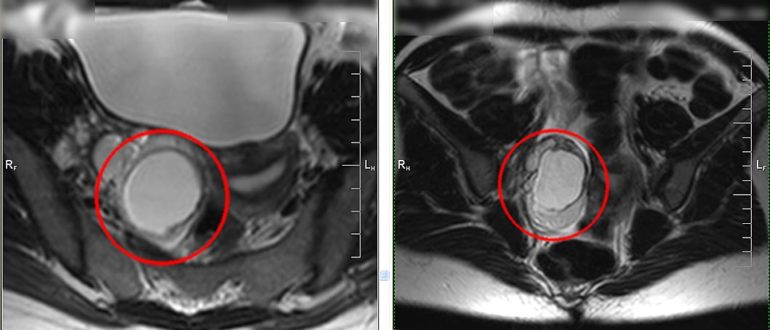

МРТ малого таза

Мрт малого таза в Балашихе — 5000 руб Основными наиболее эффективными инструментальными методами диагностики заболеваний органов малого таза являются МРТ, КТ и УЗИ. С особенностями данных методов при…